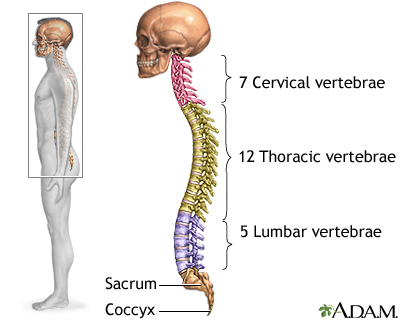

A lumbosacral spine x-ray is a picture of the bones (vertebrae) in the lower part of the spine. This area includes the lumbar region and the sacrum, the area that connects the spine to the pelvis.